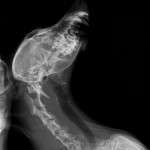

In urma investigatiilor, veterinarul a descoperit multe probleme la bunicuta Madalina, care e o catelusa in varsta de peste 10 ani: are si cataracta, o hernie f urata si mare, partii de jos a mandibulei ii lipseste o parte, un picior din spate e luxat iar cel din fata care este sucit e in urma unei traume mult prea vechi pentru a i se mai putea face ceva, oasele i s-au sudat asa din pacate. De faptul ca era plina de capuse pana si in urechi nu mai vorbim.